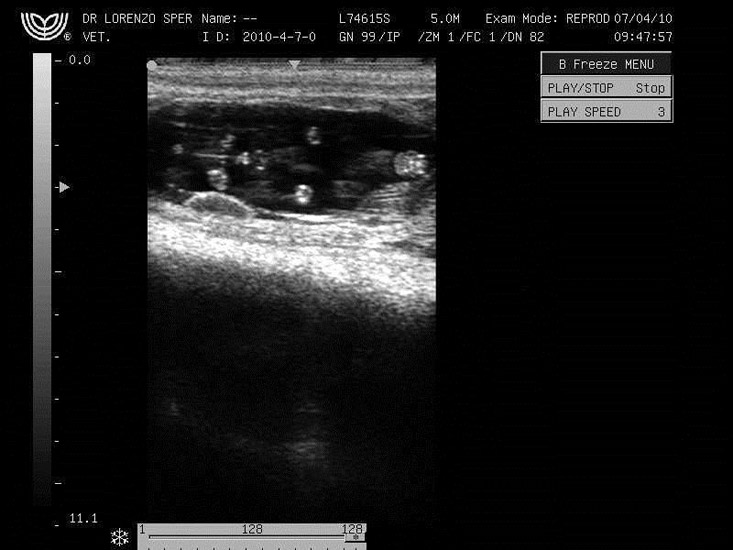

A sexagem é feita em animais com uma idade gestacional de 60 a 70 dias, tempo este que permite a visualização dos tubérculos genitais. Estas estruturas embrionárias se desenvolverão e na fêmea dará origem ao clitóris (Figura 1) e no macho ao pênis (Figura 2). Esta estrutura aparecerá no monitor de forma bilobular, hiperecóica (tom de cinza denso). No macho o tubérculo genital fica situado na base da inserção do umbigo, já na fêmea, o tubérculo genital situa-se entre os membros posteriores.

As dificuldades encontradas pela técnica é a necessidade de um médico veterinário capacitado com conhecimento da anatomia e posicionamento do aparelho reprodutor para conseguir ter uma imagem que permita a correta sexagem. O posicionamento ventral do feto é fundamental para evidenciar os tubérculos genitais.

O tempo gestacional também é uma dificuldade encontrada pelos técnicos de campo, sendo a faixa entre 60 e 70 dias a mais indicada, podendo, dependo da habilidade do veterinário, aumentar esta faixa para 55 a 75 dias de gestação.